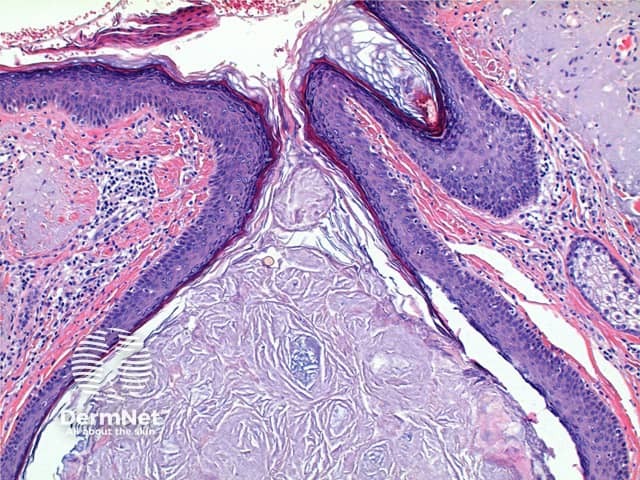

The low power view of Favre-Racouchot syndrome shows multiple comedones, dilated and plugged follicular infundibulae and epidermal cyst formation (Figures 1 and 2). This is set in a grossly solar damaged epidermis, which forms large nodules in the superficial dermis (Figure 3). The comedones are filled with compact keratinous material, while the epidermal cysts contain more loosely arranged laminated keratin (Figures 4 and 5).

Figure 4

Figure 5